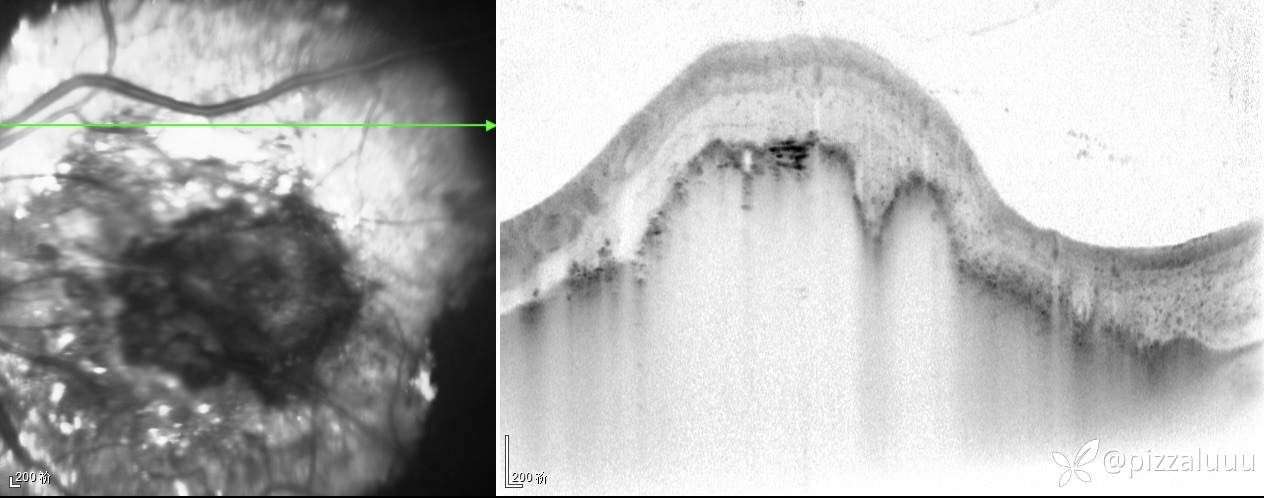

左眼轻度外斜,各位老师考虑这是什么病变?今天只做了这两项检查

玻璃体清,后极部球壁局限隆起,表面粗糙,其内回声不均